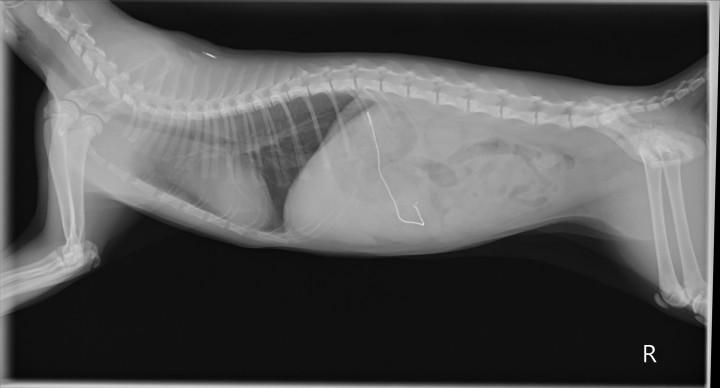

異物を飲み込んだ猫